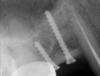

samsonov Опубликовано 2 июня, 2012 Автор Поделиться Опубликовано 2 июня, 2012 Коллеги , спасибо за советы,удалили 48,получилось с ветви достаточно объёма,будем ждать... Ссылка на комментарий

samsonov Опубликовано 2 июня, 2012 Автор Поделиться Опубликовано 2 июня, 2012 клык удалили?Стоит як памятник нерукотворный на своём месте))) Ссылка на комментарий

samsonov Опубликовано 8 июня, 2012 Автор Поделиться Опубликовано 8 июня, 2012 фотки -не очень.Маленькая compensation Ссылка на комментарий